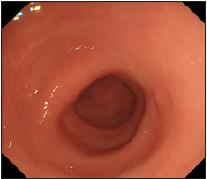

About two months later, sigmoidoscopy demonstrated that rectal IH disappeared (Figure 4). Cecal cancer operation was performed and examined as stage I/radical excision by histological diagnosis. Now, four years later, rectal IH and cecal cancer have not relapsed.

Figure 4: Sigmoidoscopy demonstrated that the rectal mass disappeared about two months later.